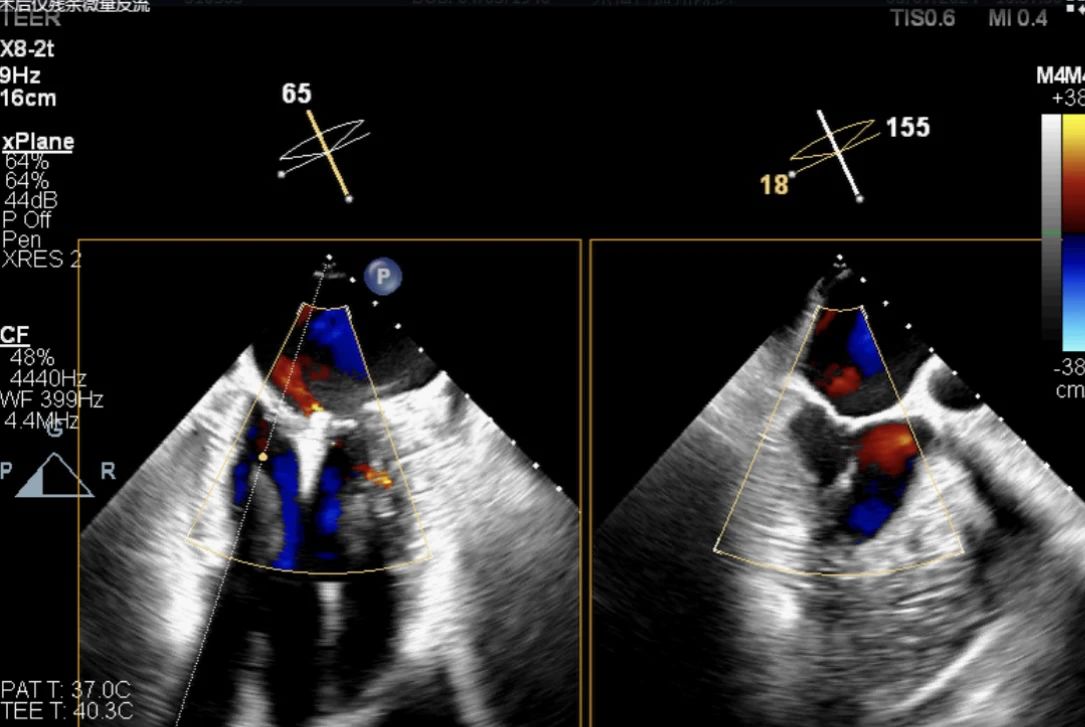

術后僅殘余微量反流